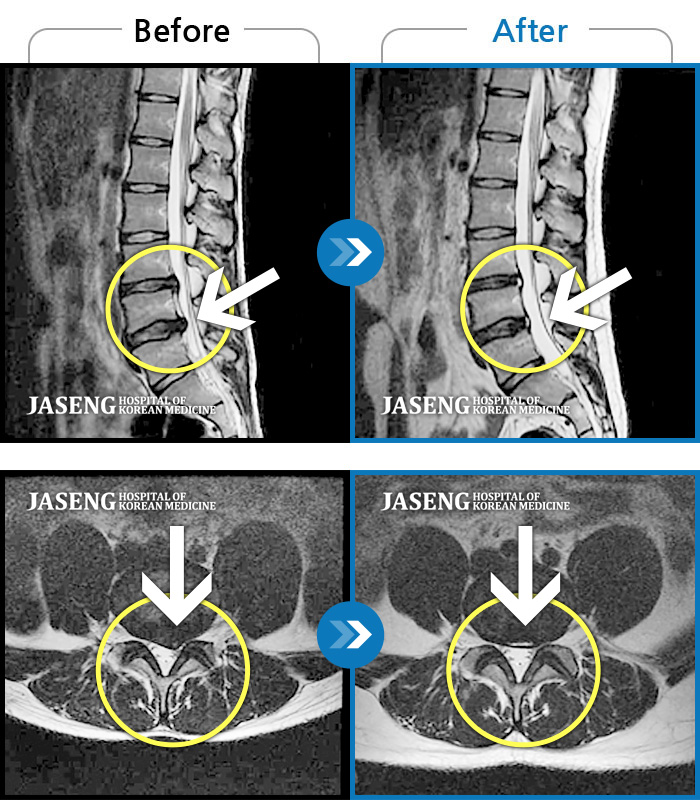

허리디스크

안산 · 김민수 원장

어떤 자세에도 통증이 지속되었다.

촬영시기

2018.10.25 ~ 2024.06.19

2024.07.31